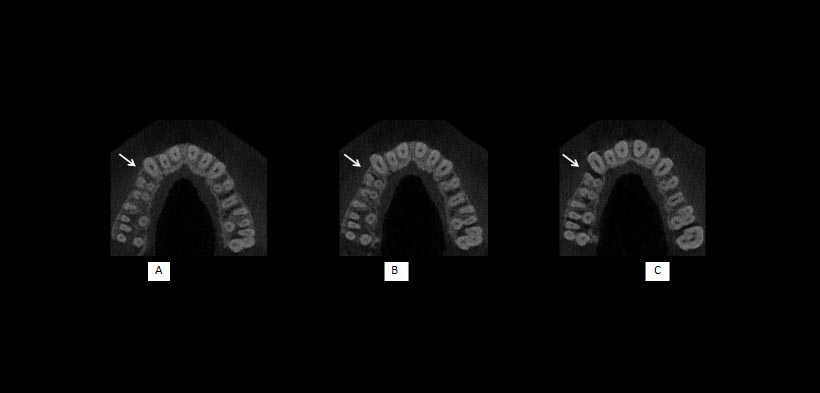

Un parámetro importante para la evaluación de la altura ósea es la distancia que existe entre la cresta del hueso alveolar a la unión del esmalte con el cemento (UCA). En la literatura existen amplias variaciones de la normalidad con respecto a ésta altura, que van desde 1 mm a 3 mm, aunque una distancia de 2 mm es más ampliamente aceptada como normal. En adultos jóvenes, la altura media del hueso en relación con la UCA es 1,4 mm y para las personas mayores de 45 años, este promedio se amplía a 3 mm (fig 1, 2, 3).

Fig 3. Cortes axiales de una tomografía que ilustran la presencia de defectos óseos combinados (flechas blancas) en la superficie mesial del diente 14. (A) No hay evidencia de defecto, (B) defecto con tres paredes restante y (C) la progresión del defecto en la dirección cervical con una pared restante.